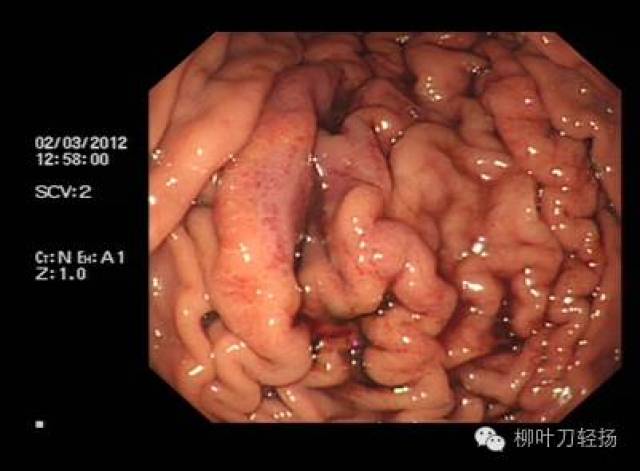

我国食管静脉曲张分级方法,按照食管静脉曲张形态及出血危险程度分为轻中重三级,具体如下1轻度曲张的静脉直径小于3mm,最初局限于食管下段,曲张呈直线形或略有迂曲无红色征2中度曲张的静脉直径在36mm,常累及食管的中段,管静脉曲张呈直线形,略有迂曲有红色征,或食管静脉曲张呈蛇形迂曲隆起但无红色征3;诊断方法内镜检查是确诊食管胃底静脉曲张的金标准,可直接观察曲张静脉的形态大小及范围,并评估出血风险影像学检查如腹部超声CT可辅助评估肝脏病变程度及门静脉高压状态,为治疗方案提供依据治疗原则治疗需个体化,依据病情严重程度肝功能状态选择方案药物治疗非选择性β受体阻滞剂如普萘。

头晕门静脉高压引发的食管静脉曲张可导致血压升高,患者可能出现头晕症状若病情严重,可能引发意识丧失甚至昏迷这种头晕与普通疲劳性头晕不同,需结合其他症状综合判断大便异常食管静脉曲张常由肝病或胃病引起,这些基础疾病本身可能导致大便异常患者可能发现粪便呈黑色或柏油色,这是消化道出血的典型;食管静脉曲张破裂出血是由于肝硬化失代偿期门脉高压导致的静脉曲张破裂所引起的消化道大出血以下是关于该病症的详细解释病因肝硬化失代偿期食管静脉曲张是肝硬化失代偿期的一种严重并发症门脉高压由于肝脏功能受损,门脉系统内的血液回流受阻,导致门脉压力升高,进而引发食管静脉曲张破裂机制;食管胃静脉曲张破裂出血是肝硬化门静脉高压最常见的并发症由于曲张的静脉管壁薄,且缺乏弹性收缩能力,一旦破裂,血液难以自行止住,出血量大且迅速,这会导致患者短时间内出现大量失血,进而引发休克等严重后果,所以该并发症的死亡率较高临床上对于食管胃底静脉曲张,尤其是已经出现破裂出血的情况;这导致静脉扩张,不能像正常情况那样收缩,形成曲张具体来说,静脉壁失去弹性,血液积累过多,使静脉直径超出正常范围,这就形成了所谓的食管静脉曲张这种病症并非仅限于食管,任何静脉回流受阻都可能导致此问题,但在门脉高压的病人中,食管静脉曲张尤其常见,且被视为严重并发症的一个标志;对于轻度食管静脉曲张,通常可以通过多种方法有效控制病情,减少出血风险药物治疗可降低门脉压力,预防静脉曲张破裂出血内镜下治疗可通过注射硬化剂或套扎等方式使曲张静脉闭塞手术治疗则通过切除部分胃或脾等降低门脉压力这些方法在早期干预中效果显著,多数患者可达到临床缓解但严重病例或合并其他。

临床观察对于轻度曲张的患者,可以首先考虑临床观察,密切注意病情变化药物对症治疗临床上常选用β1受体阻滞剂,如普萘洛尔,给予口服治疗,剂量通常为10mg,1天2次定期复查需要定期复查肝脏彩超和胃镜检查,以监测门静脉扩张的程度和食道静脉曲张的变化中度食道静脉曲张内镜下食管静脉曲张套扎术。

它是肝硬化门脉高压的主要临床表现之一食管胃底静脉曲张的发生与肝脏病变密切相关,尤其是肝硬化并发症及危害食管胃底静脉曲张易引发血管破裂,导致大出血它是上消化道大出血的四大病因之一据文献统计,30%50%的患者在第一次大出血时可出现生命危险因此,食管胃底静脉曲张是一种严重的临床。